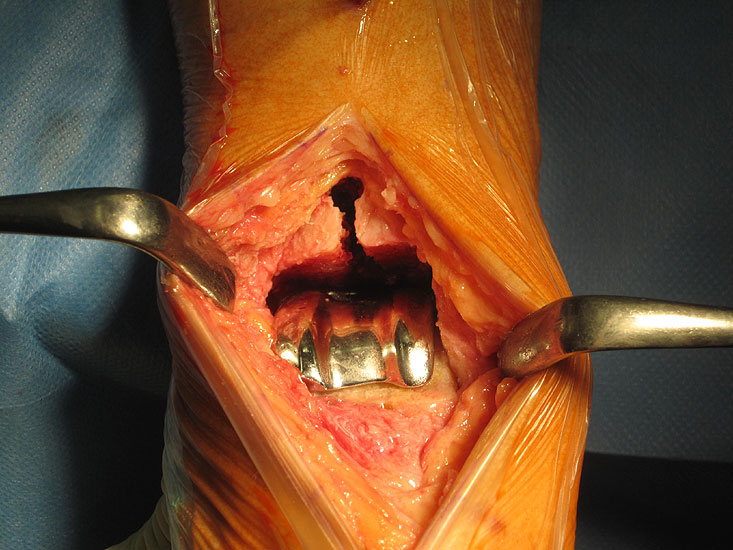

1. Wundheilungsstörung infolge einer hohen intraoperativen Druck- und Zugbelastung auf den periartikulären Weichteile; Lösung: dosierte Weichteilbehandlung durch die Hacken durch den Assistenten; aktive Erinnerungen während der Operation (Abb. 20 und 21)

2. Dorsales Auslaufen der Tibiakomponente, wenn beim Bohren der Tibiaverankerung oder beim Einschlagen der Tibiakomponente ventral zu großer Druck ausgeübt wird.